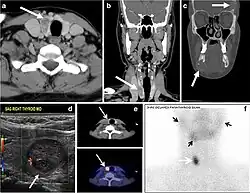

Fig. 4. A 45-year-old male patient presented with anterior mediastinal metastatic PTC lesions and occult primary on imaging. Histopathology examination of the resected thyroid gland revealed micro-foci of PTC; the largest, in the isthmus, measured 4 mm. a transverse greyscale ultrasound of the thyroid demonstrates homogeneous gland with normal echogenicity and size. No focal lesion or micro-calcifications. b Non-enhanced CT scan obtained as part of PET/CT examination shows a heterogeneous, large, relatively dense anterior mediastinal mass (white arrow) with peripheral calcification (arrowheads). Thyroid gland has normal CT appearance with no abnormal FDG uptake (not shown).[1] -

Fig. 7. A 51-year-old female patient post total thyroidectomy for PTC with elevated thyroglobulin measurement. an Axial non-enhanced CT scan of the neck at the level of the thyroid bed demonstrates a well-defined, rounded, homogenously dense soft tissue situated between the trachea and left internal jugular vein (white arrow). b Transverse ultrasound image of the neck demonstrates a well-defined, homogeneous, hypoechoic soft tissue nodule measuring 6 mm (white arrow) with no detected micro-calcifications. Biopsy showed a predominantly residual normal thyroid tissue with micro-foci of PTC.[1] -

Fig. 8. A 48-year-old male patient post total thyroidectomy with PTC recurrence. a Transverse greyscale ultrasound of the neck demonstrates a left thyroid bed heterogeneous, predominantly hypoechoic irregular lesion with calcifications (white arrow). b A spot image of iodine 123 total body scan of the neck demonstrate a focus of abnormal radiotracer uptake at the left thyroid bed (Black arrows) between the annotated markers. c Enhanced axial CT scan of the neck demonstrates an enhancing large left thyroid bed mass (white arrow) with no calcifications. The lesion exerts a mass effect on the oesophagus (black arrow) and is inseparable from the trachea.[1] -

Fig. 9. A 58-year-old male patient with persistence PTC at thyroid bed with hypervascular nodal metastasis. a–c Transverse greyscale and colour Doppler neck ultrasound demonstrate hypoehoic soft tissue in the left thyroid bed (white arrow in a). There are a heterogeneous enlarged lymph nodes at level 2 and 3 with markedly increased vascularity (white arrow in b and c). d–f Enhanced axial CT images of the neck demonstrate a 2.7 × 1.4 cm hypodense soft tissue lesion anterior to the left carotid sheath (white arrow). There are left-sided enhancing abnormal and enlarged lymph nodes at cervical level 2 and 3 (black arrows).[1]